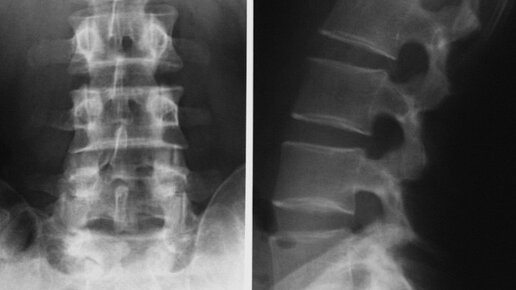

Итак, что из себя представляет рентген пояснично-крестцового отдела позвоночника? Это стандартное 2-х мерное рентгеновское исследование, проводимое в двух проекциях(прямая и боковая). Исследование проводят для определения лордоза, кифоза, остеохондроза, можно увидеть грыжу, различные новообразования(злокачественные, доброкачественные), а так же травматические повреждения. Помимо этого, можно выявить врожденные аномалии. Если вы получили заветное направление на рентген, то не спешите сразу бежать в отделение лучевой диагностики...